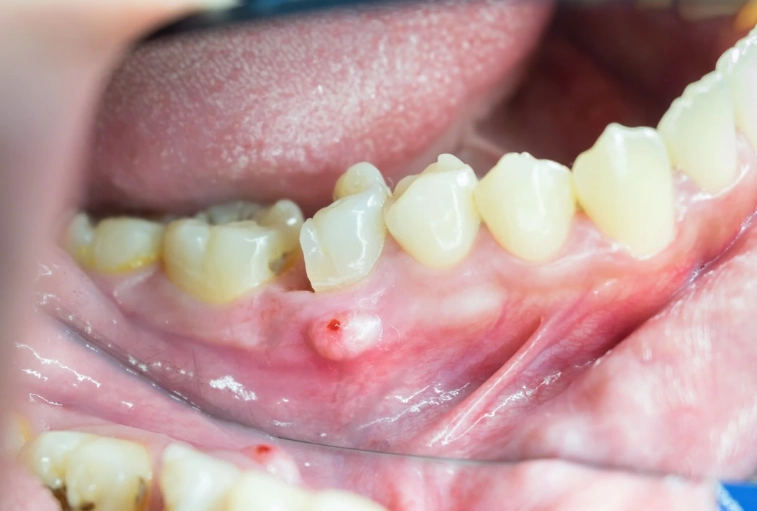

Antibiotics for a periapical abscess are typically reserved for when the infection shows signs of spreading beyond the little area around the tooth root. Your dentist is looking for what we call "systemic involvement." Here's what that looks like:

- Swelling that's spreading: Not just a little gum bump. We're talking cheek swelling, under the jaw, or even near the eye if it's an upper tooth. This is a red flag.